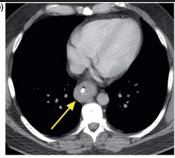

CT Scan

CT scans showed thickening of the distal esophagus.

an enlarged lymph node in the region of the gastrohepatic ligament, extending to the celiac axis.